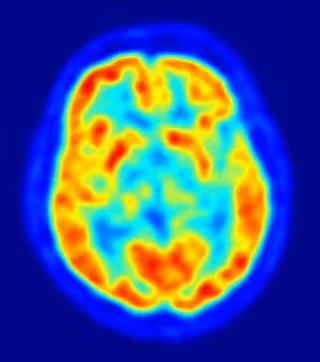

Localizan la región del cerebro responsable de percibir las estructuras en 3D

La capacidad de percibir la realidad en tres dimensiones se desarrolla en la corteza cerebral temporal inferior, donde la actividad neuronal en esta región crea una representación del objeto donde se capta además su profundidad, según un estudio llevado a cabo por expertos de la Universidad de Leuven en Bélgica.

El hallazgo, publicado en la revista 'Neuron', ha sido realizado en primates. "La corteza temporal inferior es responsable del reconocimiento de objetos. Tanto en monos como en humanos, cuando existe una lesión en ella se puede padecer agnosia, la incapacidad para reconocer objetos o estímulos ya aprendidos", aclara Janssen.

Los investigadores estimularon grupos de neuronas en la corteza temporal inferior con pequeñas descargas mientras trataban de decidir si una superficie era cóncava o convexa. "Al observar un balón de fútbol, por ejemplo, inmediatamente sabemos que tiene profundidad, que no es plano sino convexo y con estructura tridimensional", explica.